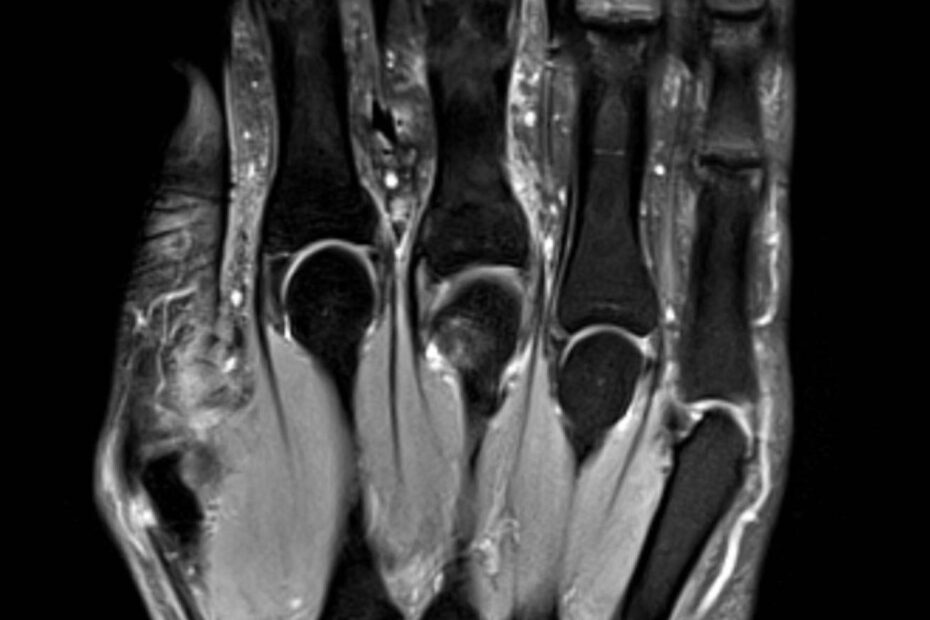

Eine Magnetresonanztomographie der Hand, auch MRT Hand genannt, ist ein bildgebendes Verfahren, das mithilfe von Magnetfeldern detaillierte Bilder der Hand und des Handgelenks erzeugt. Die MRT Hand wird häufig eingesetzt, um Verletzungen, Entzündungen oder andere Probleme im Handbereich präzise zu diagnostizieren. Die MRT der Hand ist besonders nützlich, da sie im Gegensatz zu Röntgenaufnahmen auch … MRT Hand weiterlesen